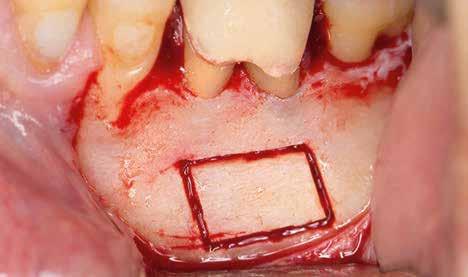

A beavatkozás során helyi érzéstelenítésben teljes vastagságú mucoperiostealis lebenyt képeztünk, és a sablon segítségével bejelöltük a preparálandó csontablak határait. Az ablak széleinek megfelelően Piezotome CUBE LED kézi-darabbal (ACTEON) a kortikális teljes vastagságában vágást ejtettünk, majd az így kapott csontlemezt (ablakot) eltávolítottuk (1. e–h. ábra), és ezt követően steril fiziológiás sóoldatba helyeztük. A rezekció elvégzését követően (1. i. ábra) a mezialis csatornákat ultrahangos eszközök segítségével (NSK) retrográd irányból preparáltuk, majd az így kialakított mélyedésbe retrográd gyökértömést készítettünk. A tömés anyagául az EndoSequence BC RRM Fast Set Putty-t (Brasseler) választottuk. A tömés elkészítését követően a csontablakot visszaillesztettük, és a stabilizálása érdekében a vágásoknak megfelelően kialakult résekbe kollagén szivacsokat (Collagen Tape, Zimmer Biomet) helyeztünk (1. j-k. ábra). A lebenyt 6/0-s Prolene varratokkal (Corpaul) rögzítettük.

A kétéves kontroll során elvégzett klinikai és radiológiai vizsgálat (CBCT-felvétel) a periapicalis elváltozások megszűnését és a corticalis csontállomány tünet- és szövődménymentes gyógyulását